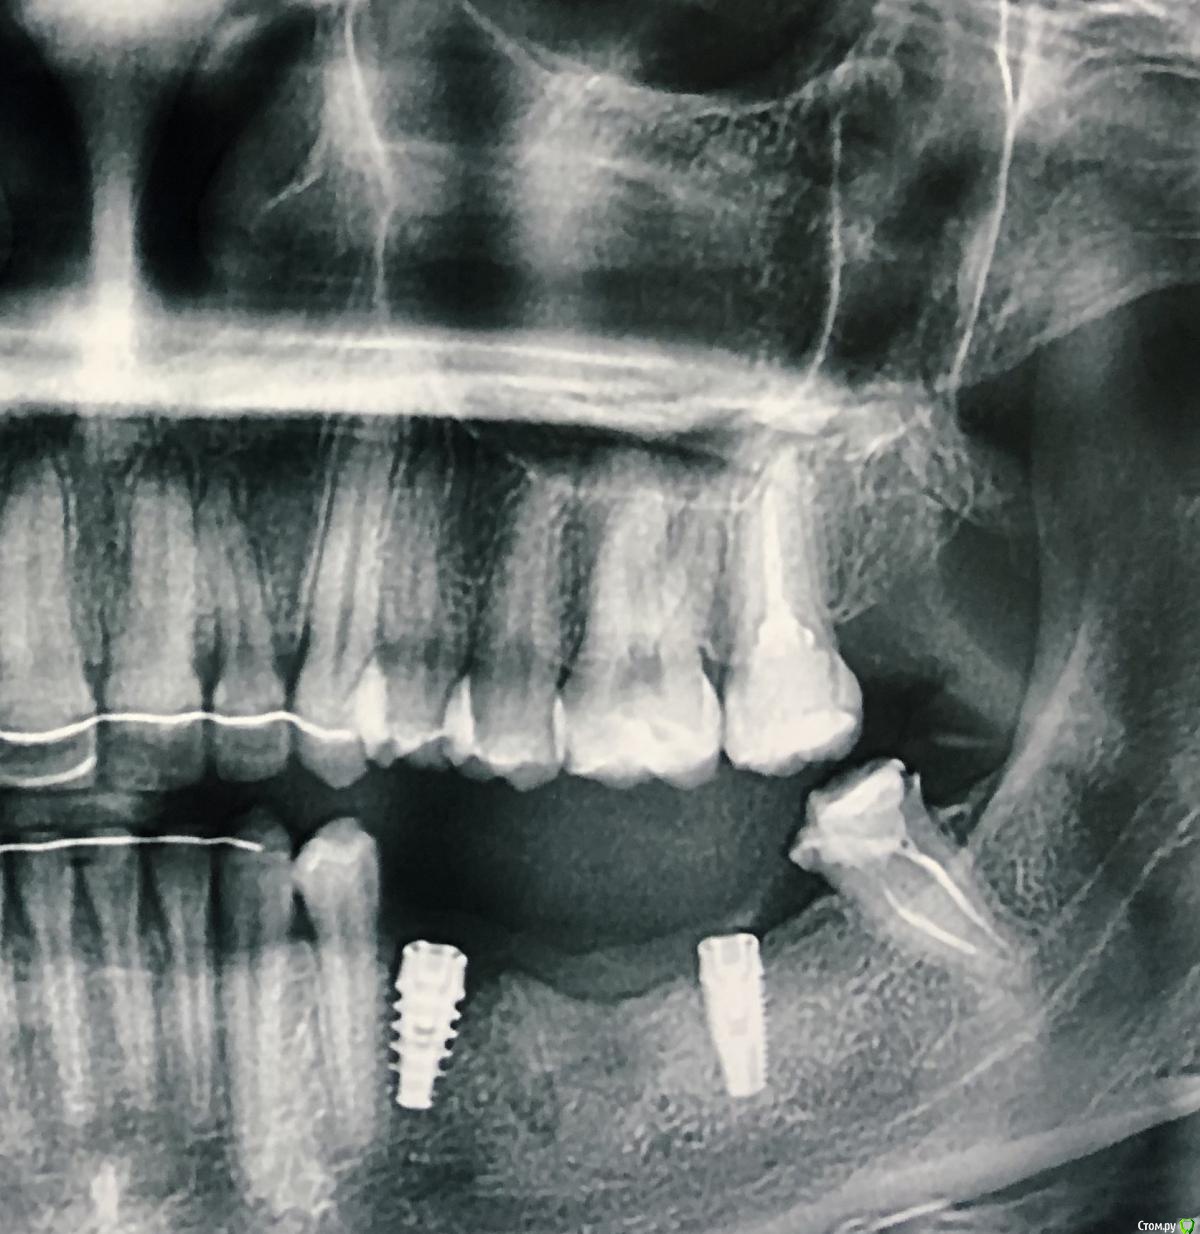

RaisaS Опубликовано 20 декабря, 2019 Поделиться Опубликовано 20 декабря, 2019 Добрый день! Нужен совет! Поставили 2 недели назад имплант, сделала снимок ОПТГ , по нему видно, что встал он слишком близко к корню соседнего зуба. Ничего не болит, не беспокоит. Ранее уже был неудачно установлен этот имплант , также близко к корню зуба. Пришлось удалять и имплант и зуб. Через 3 мес после восстановления была проведена новая операция. Подскажите, что делать! Врачу уже доверия особого нет... Спасибо! Ссылка на комментарий

red_butler Опубликовано 20 декабря, 2019 Поделиться Опубликовано 20 декабря, 2019 расстояние до зуба нормальное, но оба импланта не заглублены должным образом 3 Ссылка на комментарий